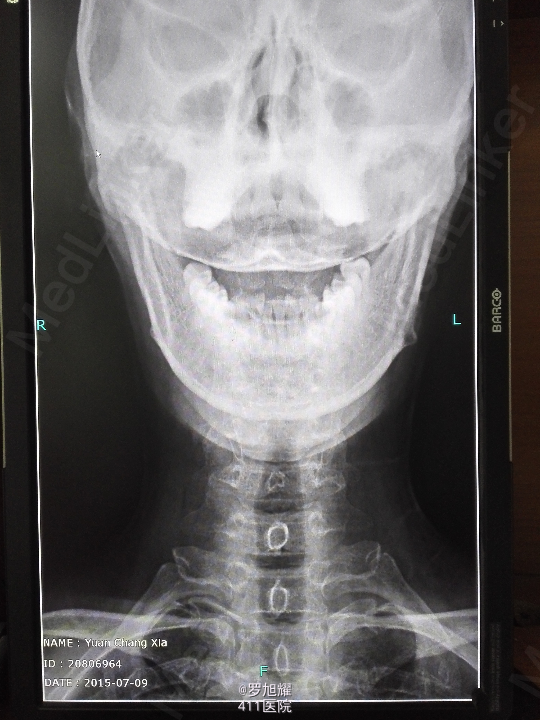

右侧躯体麻木1年,右上肢及下肢麻木2月余。 查体:颈椎活动受限,右上肢肘关节以远痛温觉减退,右侧胸4平面以下痛温觉及触觉减退,四肢肌力尚可,右侧霍夫曼征阳性,右侧上下肢所有腱反射亢进。 颈椎X线示:颈2椎板棘突缺如,颈3棘突肥大增高。 颈椎CT示:颈2椎板棘突缺如,颈3棘突肥大增高,颈2/3椎间盘突出,左侧颈2残留部分椎板进入椎管。枢椎齿突增生,寰枢关节退变。 颈椎MRI示:颈2/3椎间盘突出,左侧颈2椎板进入椎管,颈髓受压变性。

查体:颈椎活动受限,右上肢肘关节以远痛温觉减退,右侧胸4平面以下痛温觉及触觉减退,四肢肌力尚可,右侧霍夫曼征阳性,右侧上下肢所有腱反射亢进。 颈椎X线示:颈2椎板棘突缺如,颈3棘突肥大增高。 颈椎CT示:颈2椎板棘突缺如,颈3棘突肥大增高,颈2/3椎间盘突出,左侧颈2残留部分椎板进入椎管。枢椎齿突增生,寰枢关节退变。 颈椎MRI示:颈2/3椎间盘突出,左侧颈2椎板进入椎管,颈髓受压变性。